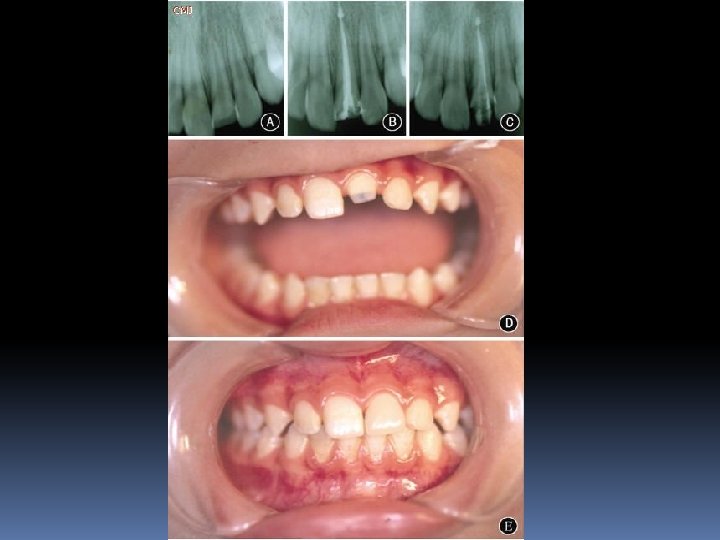

“Post-Kor” restorasyonlarının endikasyonları 1. Aşırı derecedeki madde kayıplarında, 2. Travma sonucu oluşan kron kırıklarında 3. Erozyon gibi aşınmalar sonucu derin madde kayıplarında 4. Diş akslarının düzeltilmesinde, 5. Teleskop kronların kullanımında, dişlerin “post-kor” yada yalnız “kor” alt yapısı ile restore edilmesi gerektiğinde.

Kavite duvar sayısı Yapılması Gereken En az 1 mm kalınlığında 4 duvar varlığı Post gerekmez En az 1 mm kalınlığında 3 duvar varlığı Adeziv dolguların kullanılmasında post gerekmez 1 ya da hiç duvar bulunmaması Post gerekir.

Post kor yapılmaya karar verildiyse Kanal içinde kalacak post boyu en az kron boyuna eşit olmalıdır. Daha da tercih edileni 1 birim kron boyuna 2 birim post uzunluğudur. DL ≥ CL Ya da tercihen DL = 2 CL AF ≥ 4 mm

Ferrule effect (Ferrule Etkisi) Bir diş dokusunu saran kuvvetler demektir Eğer kron, kor yapının apikal marjinine kadar uzanır ve sağlam diş yapısını 360 derece sarar ise kron vertikal fraktürden korunmuş olur Yapının kırılmaması ve ferrule effect için en az 1 mm sağlam diş dokusu çepeçevre kron altında bulunmak zorundadır